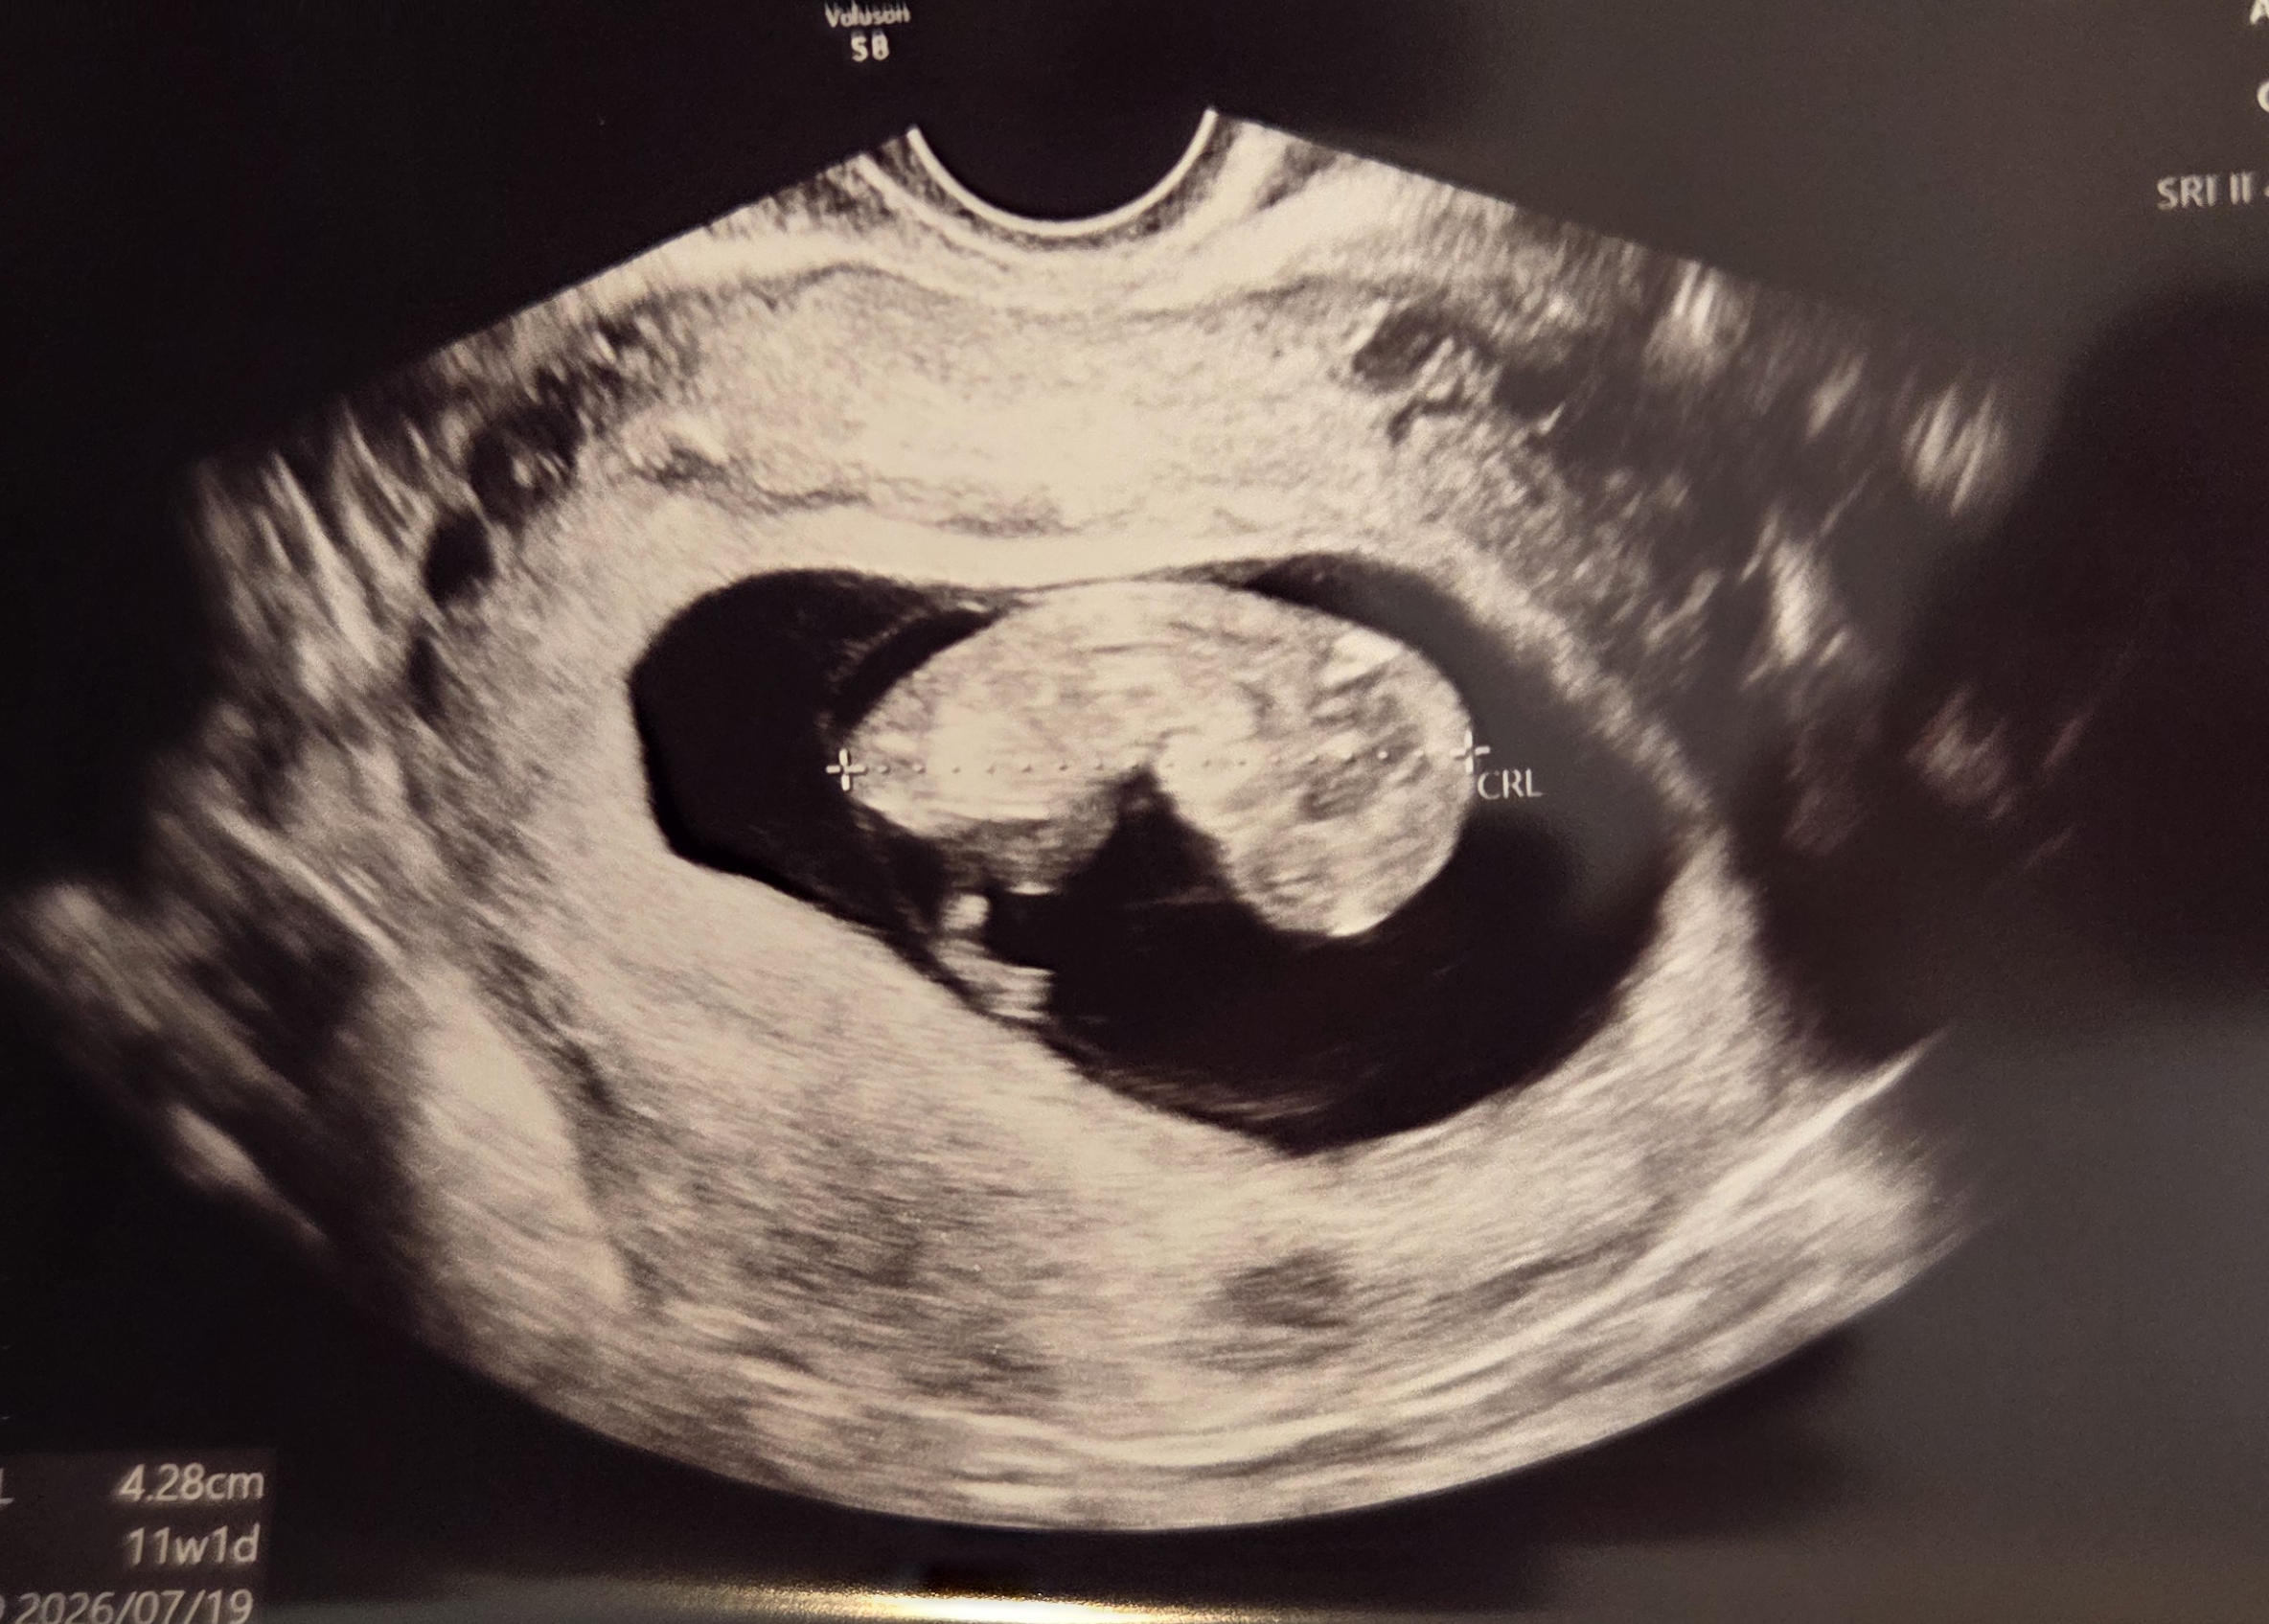

반흔의 걱정 속에서도, 첫 시도에 이어진 착상 - 희망나눔